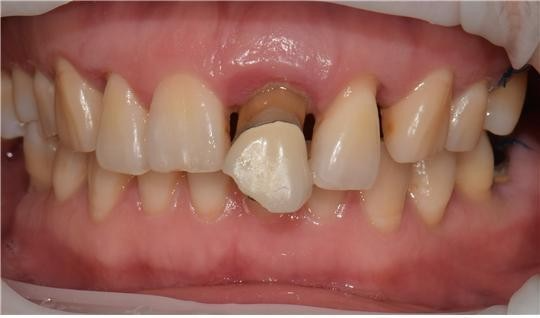

치료명 : 신경치료 및 지르코니아관 수복, 임플란트

c.c 상악 전치부 상담 원하심. 치아 사이 벌어져 있음

#21.22 정출, #21발치 설명드림. #131211X2223 브릿지 진행

#22 신경노출로 신경치료 진행함.